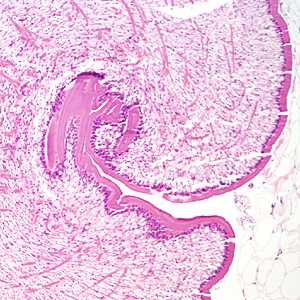

A 68-year-old woman underwent a routine screening mammogram, which revealed calcifications in the right breast. Biopsy specimens were collected and sent to Pathology for histological work-up. Figures A–D show what was observed at 20x, 100x, 200x, and 400x magnification respectively by the attending pathologist on one of the slides stained with hematoxylin and eosin (H&E). What is your diagnosis? Based on what criteria?

Figure A

This was a case of sparganosis caused by the third-stage plerocercoid larva (sparganum) of a cestode in the genus, Spirometra. Diagnostic features include:

- a thick tegument.

- presence of calcareous corpuscles.

- absence of defined protoscoleces.